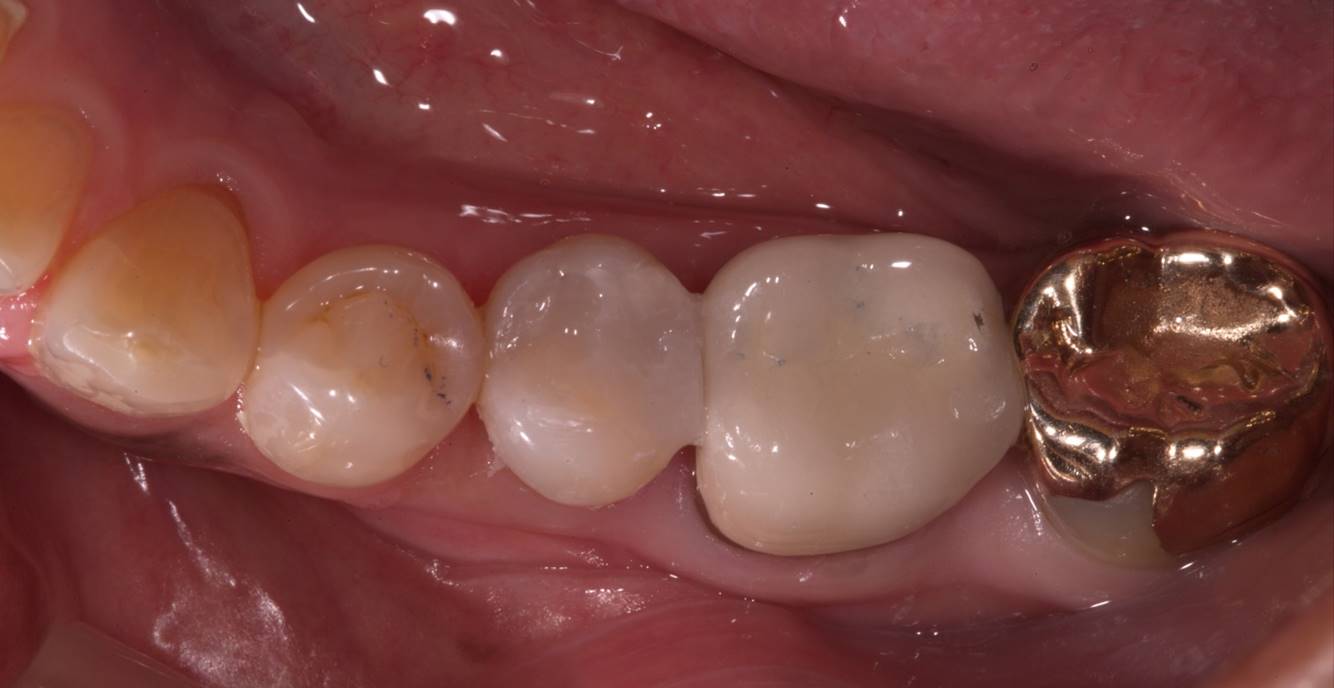

Fig 5. Preoperative view of a patient who presented with two defective amalgam restorations requiring replacement.

Figure 5